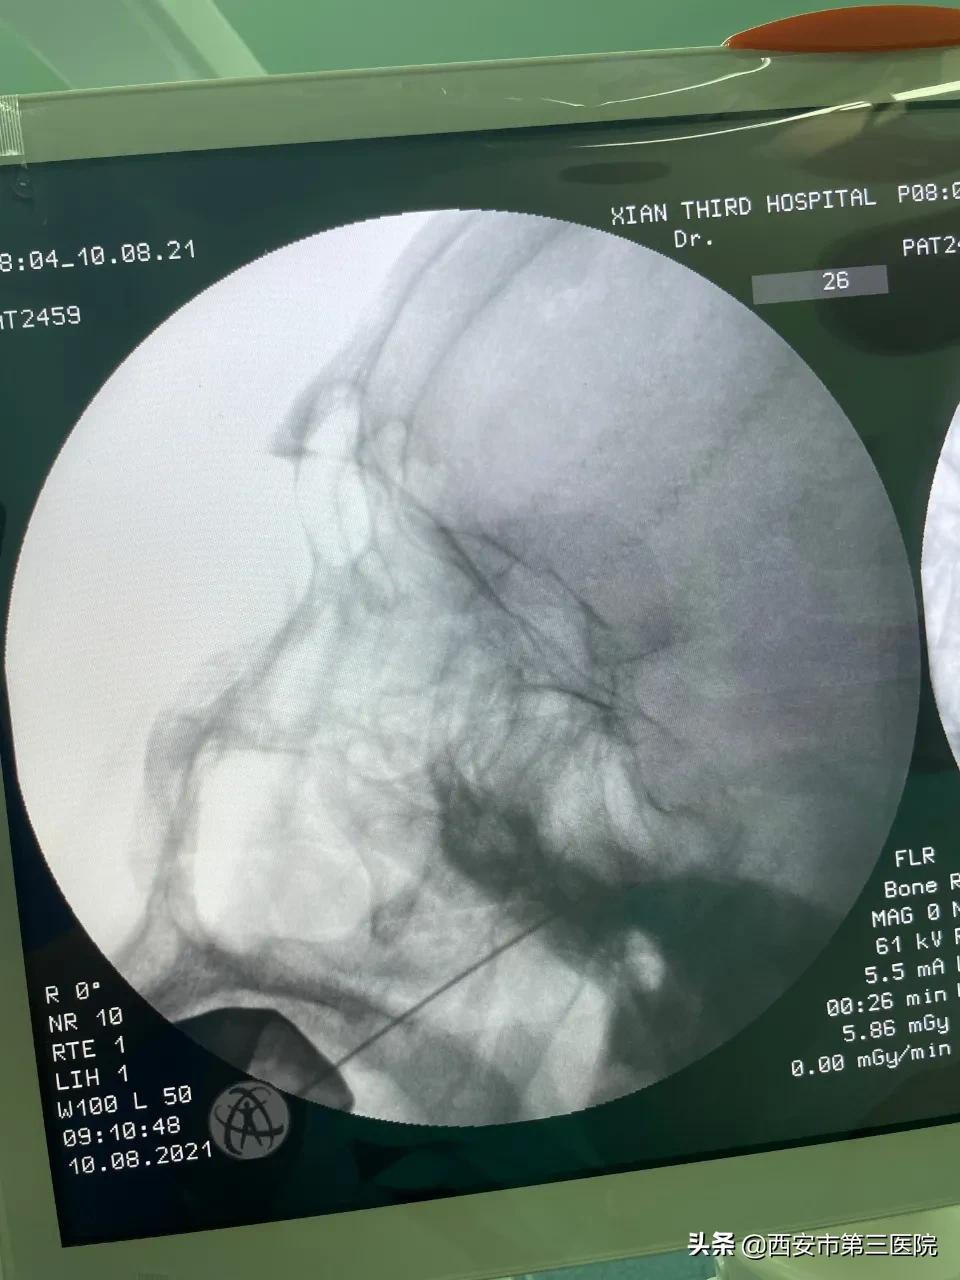

▲穿刺针经右侧卵圆孔外侧进入Meekel腔(正位图像)

▲穿刺针经右侧卵圆孔外侧进入Meekel腔(侧位图像)